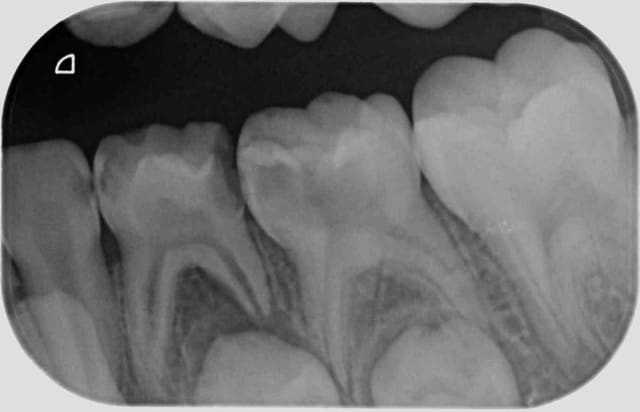

Ca m'intéresse, ça.

Dans le cas de la radio ci-jointe, penses-tu pouvoir faire les 3 soins avec un point d'injection ? En interradiculaire de la 74 ?